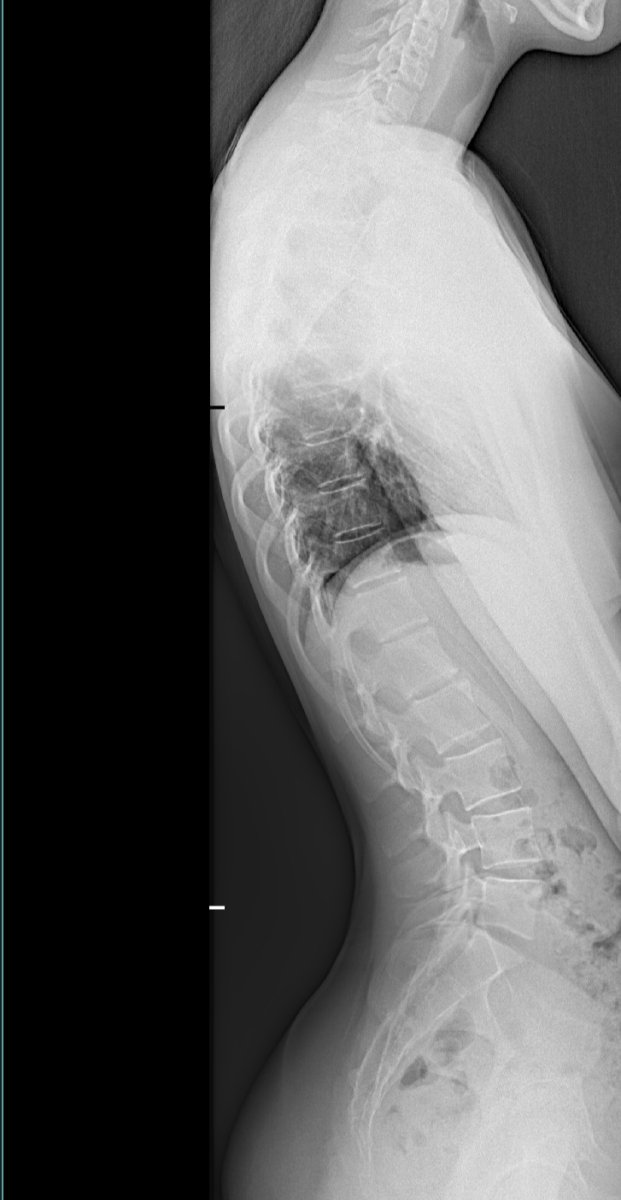

Dacht ik ook ja. Ifbb pro Mascha Tieken heeft dat ook.Je kunt met training veel verbeteren en evt een brace. oud forumlid @Tatsu had het geloof ik ook, maar een goede orthopeed kan je gericht advies geven. Neem ook aan dat je via een orthopeed foto's hebt laten maken

Dat zal de orthopeed je aangeven. en herstel heb ik al aangegeven, zeker omdat ze nog niet volgroeid is.Weet iemand of dit een erge vorm van scoliose is? Men drukt dit uit in graden. Dit lijkt me maar een paar graden. Zou het kunnen dat met sport en en brace dit bijna volledig weggaat? Ze is bijna 15 en 1m60 ongeveer

Nee volgens mij niet extreem maar lijkt wel forward head posture schouders naar voren enzo. Zou daar ook op letten. Of moest ze deze houding aanhouden voor de foto?Weet iemand of dit een erge vorm van scoliose is? Men drukt dit uit in graden. Dit lijkt me maar een paar graden. Zou het kunnen dat met sport en en brace dit bijna volledig weggaat? Ze is bijna 15 en 1m60 ongeveer

Weet iemand of dit een erge vorm van scoliose is? Men drukt dit uit in graden. Dit lijkt me maar een paar graden. Zou het kunnen dat met sport en en brace dit bijna volledig weggaat? Ze is bijna 15 en 1m60 ongeveer

Zou het kunnen dat ze dit heeft ontwikkeld door het kunstschaatsen. Altijd op dat ene been, en het andere been steil naar achteren en naar boven...vele jumps....thuis trainde ze uren lang in de woonkamer...altijd dus die schuine stand.... Ze is altijd zeer sportief geweest.Als ik zo vergelijk met andere röntgenfotos dan is dit heel mild, maar goed, dat kan de arts wel vertellen. Lijkt mij dat er nog veel mogelijk is vanwege haar leeftijd. Sterkte in ieder geval!

Zou het kunnen dat ze dit heeft ontwikkeld door het kunstschaatsen. Altijd op dat ene been, en het andere been steil naar achteren en naar boven...vele jumps....thuis trainde ze uren lang in de woonkamer...altijd dus die schuine stand.... Ze is altijd zeer sportief geweest.